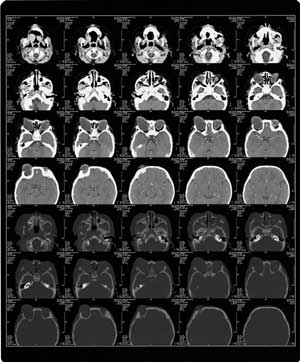

C T: 双侧眼球增大,形态不规则,成分叶状,并向前突出。双眼晶体未显示,右眼视神经未显示。(见附图CT)